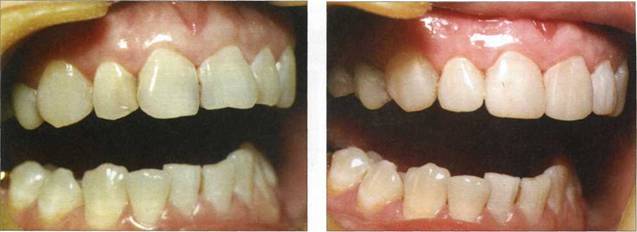

Клинический пример 23

Пациентке 19 лет. Флюороз. Произведена реконструкция первых премоляров, клыков, резцов верхней челюсти материалом "Charisma" фирмы "Heraeus KULZER".

Рис. 789. Исходная клиническая ситуация

Рис. 790. Исходная клиническая ситуация